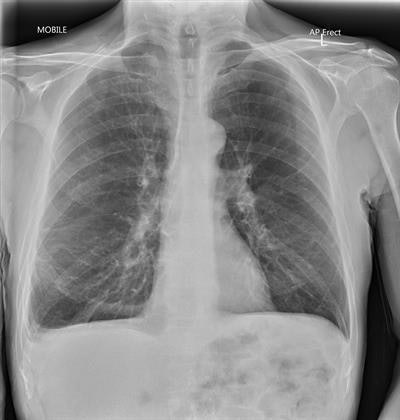

Our radiologists were satisfied with the image quality, with 90% of images taken through glass considered diagnostic. With our parameters, the typical radiation dose to patients is the same whether the x-ray is taken through glass or not.

An example of how the technique can obtain good image quality (110 kV, 5 mAs). Reproduced with permission of ACPSEM.The technique has been established for use in the current COVID-19 pandemic, and we assessed the radiation safety accordingly. The radiographers and/or nurses do not need to wear a lead apron. This was important because of the amount of PPE they were already wearing and the infection control risks associated with sharing lead aprons.